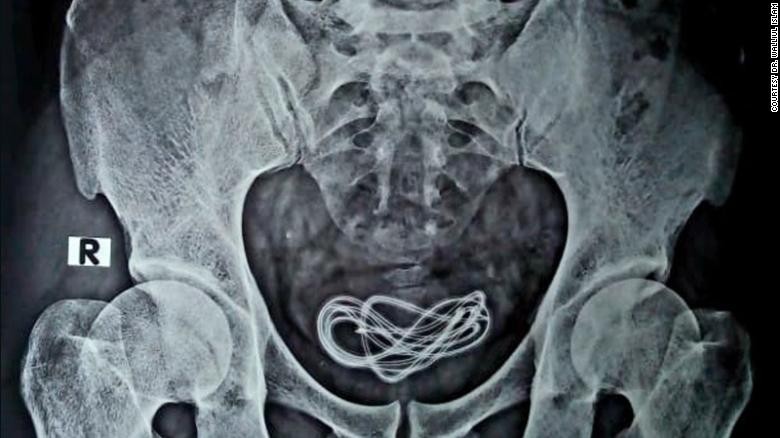

Una radiografía reveló que el hombre tenía un cable de cargador de 60 centímetros de largo dentro su vejiga, el cual fue insertado a través de su uretra, el tubo que va desde el pene a la vejiga. Sucedió en India.

Una radiografía reveló que el hombre tenía un cable de cargador de 60 centímetros de largo dentro su vejiga, el cual fue insertado a través de su uretra, el tubo que va desde el pene a la vejiga.